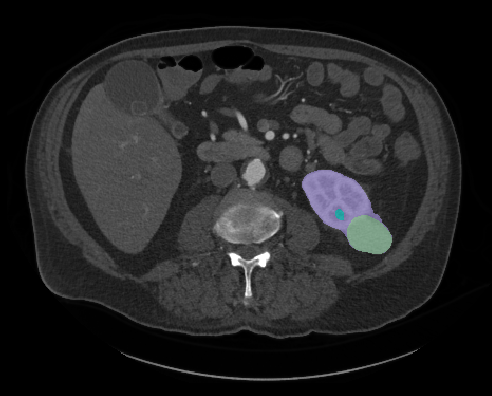

Enhanced Imaging Could Provide Quicker, More Precise Diagnosis for Malignant Kidney Tumors

With a click of a button, ARCS Scholar Nick Heller is helping radiologists identify and analyze kidney tumors within a patient’s body.

Heller is a PhD student conducting computer science research at University of Minnesota. His research focuses on using computer technology to enhance medical imaging, like a CT scan or an MRI. According to Heller, the magnified images will allow radiologists to quantify the type of tumor it is, saving time between a patient’s diagnoses and treatment.

“They will be able to measure a tumor mass, determine how big and rough they are, and whether they look distinct or blurry against the background. Medical professionals can use that information to choose the most effective treatment and predict a patient's outcome,” Heller explains.

(Courtesy: Nick Heller)